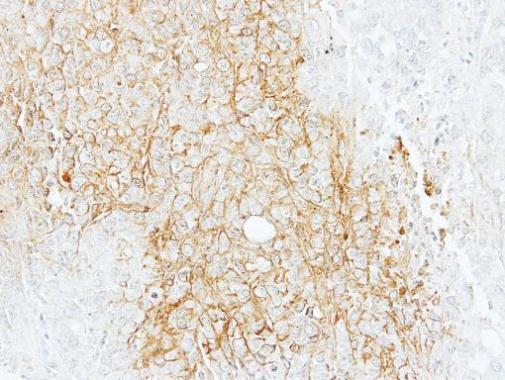

BSEP antibody [N3C1], Internal detects BSEP protein at cell membrane by immunohistochemical analysis.

Sample: Paraffin-embedded mouse liver.

BSEP stained by BSEP antibody [N3C1], Internal (GTX102608) diluted at 1:500.

Antigen Retrieval: Citrate buffer, pH 6.0, 15 min